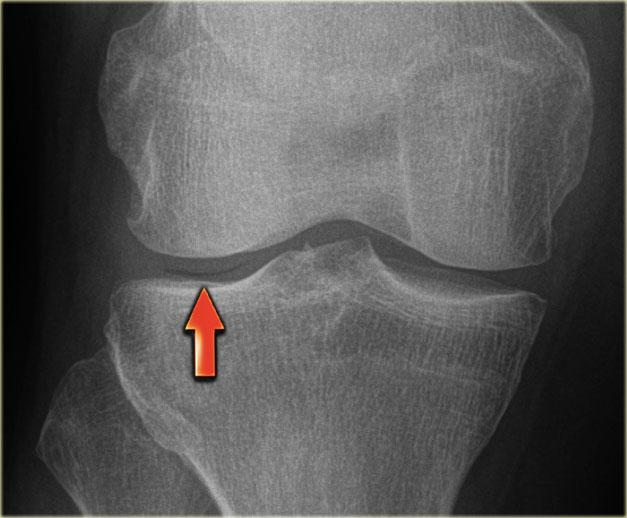

Gãy xương Segond và rách sụn chêm

Gãy xương Segond là tổn thương bong gân (avulsion) của dây chằng bao khớp bên ngoài.

Cơ chế chấn thương là xoay trong kết hợp với lực varus.

Trên phim X-quang, tổn thương biểu hiện dưới dạng một mảnh xương hình bầu dục tách rời khỏi mặt ngoài đầu gần xương chày (hình).

Gãy xương Segond có mối liên quan chặt chẽ với rách dây chằng chéo trước (75-100%) và tổn thương sụn chêm trong và ngoài (66-70%).

Trên phim X-quang, gãy xương Segond có thể dễ bị bỏ sót (mũi tên đỏ).

Lưu ý rằng còn có thêm tổn thương bong gân của dây chằng bên trong.

Tiếp tục xem các hình ảnh MRI.